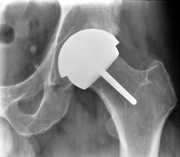

Hip resurfacing involves replacing damaged surfaces in the hip joint with metal surfaces. This procedure can be useful for patients under 65 with advanced hip disease

Hip resurfacing surgery is an alternative to standard hip replacements for patients with severe arthritis. In hip resurfacing surgery, the implant is smaller, and less normal bone is removed. Hip resurfacing is gaining interest, especially in younger patients